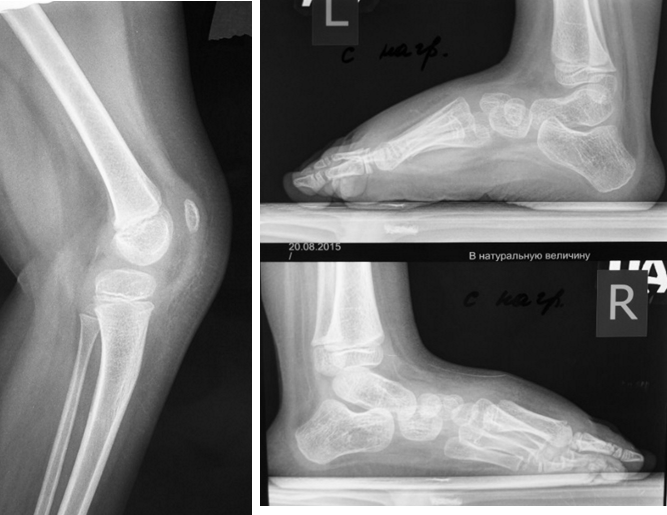

На рисунке показаны результаты надмыщелковой разгибательной остеотомии и одновременной торсионной деформации у ребенка с данной патологией.

В более поздних стадиях, когда порочная ситуация уже длительно существует и далеко зашли неблагоприятные изменения, для устранения сгибательной установки голени может потребоваться разгибательная надмыщелковая остеотомия бедра. В этой ситуации очень часто одновременно с устранением сгибательной установки голени, устраняется и торсионная деформация бедренной кости, которая часто характеризуется как наружная торсионная деформация.

ПРИНЦИПЫ ВЫПОЛНЕНИЯ ОСТЕОСИНТЕЗА непременно включают использование титановых имплантатов с необходимостью раннего блокирования, ранней вертикализации и опоры на оперированную конечность, что является общими принципами выполнения нейрохирургических операций.